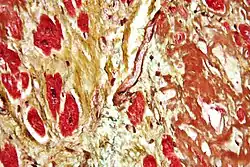

Одной из наиболее опасных форм течения ИБС и одной из основных причин смерти является инфаркт миокарда (ИМ) – некроз (гибель) участка миокарда вследствие резкого ухудшения коронарного кровотока, в большинстве случаев сопровождаемый развитием характерной клинической картины, ЭКГ - изменениями и динамикой активности маркеров некроза миокарда в крови. ИМ классифицируют по различным критериям: размер, локализация, сроки от начала развития и проч.[6]

Миокардиты – это совокупность клинических и морфологических изменений тканей сердца (кардиомиоциты, клетки проводящей системы, соединительнотканной структуры и т.д.) в случаях, когда доказано или обоснованно предполагается наличие воспалительных изменений миокарда инфекционной или аутоиммунной природы. ВОЗ и Международное общество кардиологов (ISFC) определили миокардит как воспалительное заболевание мышцы сердца, диагностированное по гистологическим, иммунологическим или иммуногистохимическим критериям. Воспалительный процесс может быть острым или хроническим и является следствием воздействия различных этиологических факторов, поражающих миокард непосредственно и/или опосредованно через аллергические иммунные механизмы[12].